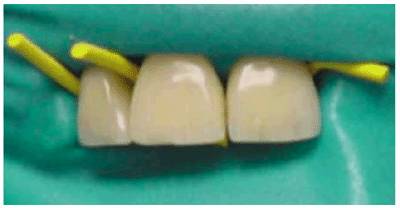

1. Floss or rubber cord ligation. Dental floss or Hygenic's rubber cord

"Wedjets" (Figure 19-39A) can be used to retain a rubber dam

when isolating a single tooth. Wedjets is a stretchable cord that is made from

natural latex. The cord, available in three sizes, is placed like dental floss

to hold the dam in place. Wedges can be used in conjunction with dental floss

or Wedjets once the dam is in place. For convenience, it is recommended that at

least one tooth on either side of the treated tooth be included in the

isolation (Figure 19-39B

Figure 19-39A: Wedjets (Hygenic), three sizes.

Figure 19-39B: Wedjets stabilizing the rubber dam and aiding in the isolation of a maxillary central incisor.